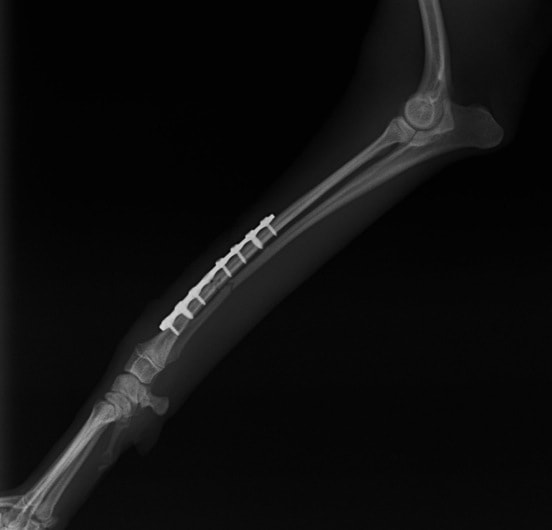

ペルシャ猫 11ヶ月齢 雄

他院にて左大腿骨遠位の成長板骨折(salter-harrisⅠ型)が認められており、治療相談を目的として来院。当院にて、キルシュナーワイヤーを用いたピンニングにより骨折部位の整復を行いました。術後の経過は良好で、現在も経過観察中です。

術後レントゲン

Arthrex社のターゲティングデバイスを用いてピンニングの位置を調整することで、確実な固定を行っています。当院ではこの手術器具以外にも、人の手術にも使用される様々な器具を導入し、手術精度を高め、また医療メーカーと新しい器具の開発、試作にも取り組んでおります。